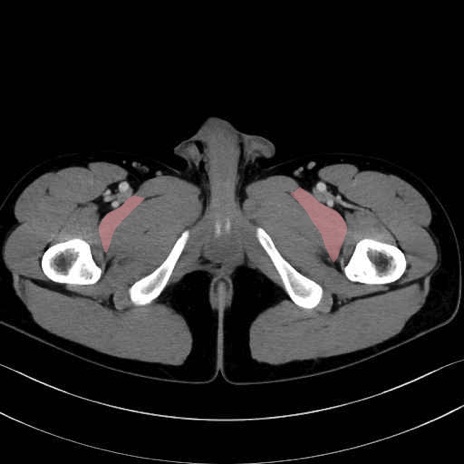

恥骨筋(pubic muscle) のCT画像の解剖

恥骨筋 (Pectineus)